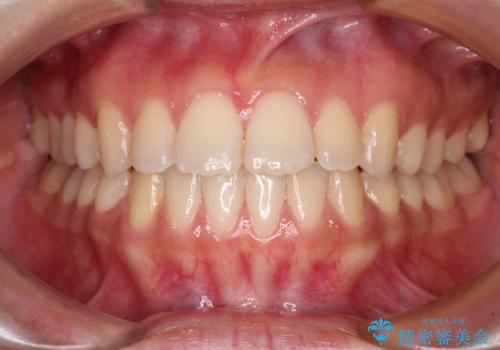

[インビザライン] 前歯のガタつき・すれ違い マウスピース矯正治療